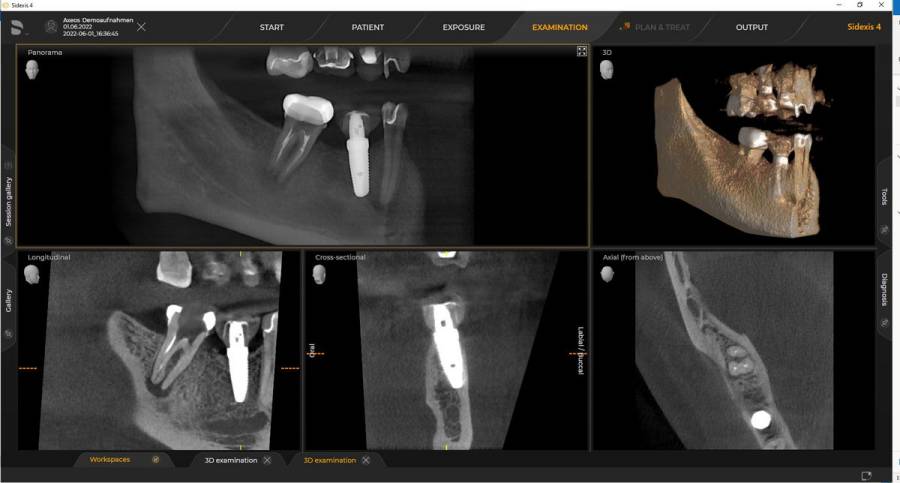

Rendelőnkben lehetőség van fogászati kisröntgen, panoráma röntgen, teleröntgen, CBCT felvétel készítésére. Az elkészített felvételeket digitálisan tároljuk rendelőnkben és szükség esetén átadjuk pácienseinknek is. A CBCT képalkotás olyan nagy mennyiségű információt és hajszálpontos részleteket is feltár, amiket semmilyen 2D-s intraorális vagy panorámaröntgennel nem lehet megjeleníteni. Segítségével pontosabb képalkotó lehetőséget biztosíthatunk a páciensek számára. Extrém felbontásával és alacsony sugárdózisával szinte tökéletes képet mutat az adott területről.

A Dentsply Sirona legmodernebb készüléke, az Axeos dual scan technológiával működik, így a fogorvosok és a szájsebészek egyszerre kaphatnak részletes képeket a fogakról és az állcsontokról, valamint a lágy szövetekről, mint például az íny vagy az idegek. Ez segíti a pontosabb diagnózis felállítását és a kezelési tervek kidolgozását. A kiemelkedő képminőség és a személyre szabott 3D mezőméretek mellett a készülék teljes mértékben a páciens kényelmére van optimalizálva.